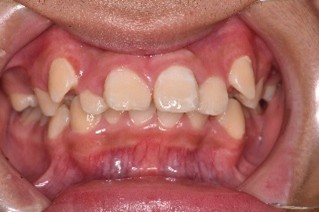

(初診時) (ワイヤー除去前) (ワイヤー除去後)

※この方はワイヤー矯正後、マウスピース矯正に移行しています

こちらの患者様は前歯の歯並び改善を目的に来院されました。患者様の歯をきれいに並べるには歯列のスペースが足りなかったため抜歯を行い、その後ワイヤー矯正から行っていきました。